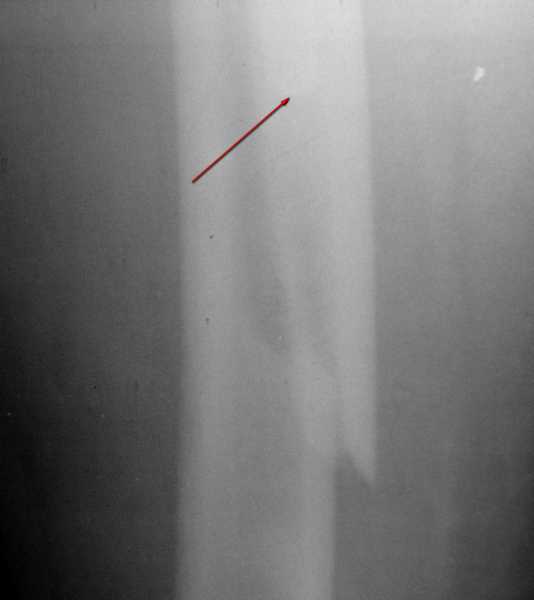

1. Представляющей наибольшую ценность из представленной информации следует считать фасные снимки №3и №4 (если считать по порядку). На снимке №3 не видны ни проксимальный отдел бедра с зоной (линией) перелома - наложение тени, ни дистальная зона (линия) перелома - область не захвачена. Снимок №4 демонстрирует дистальную линию перелома, но не показывает уровень конца ножки эндопротеза. В таких сучаях как способ можно выполнять снимок "с метками" - чтобы при при наложении снимков на негатоскопе иметь целостностное представление о всём сегменте от тазобедренного до коленного суставов.

1. На снимке №3 не видны ни проксимальный отдел бедра с зоной (линией) перелома

Там видно расхождение фрагментов, диастаз чуть медиальнее б. вертела.

Снимок №4 демонстрирует дистальную линию перелома, но не показывает уровень конца ножки эндопротеза.

Кончик ножки виден на самом верху этого снимка.

Вот фрагменты этих снимков с более различимыми областями интереса.